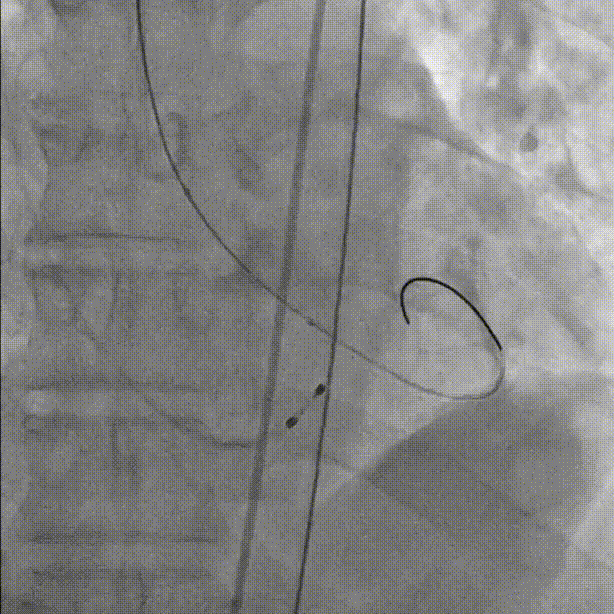

完全释放和瓣膜脱钩:

术后导管测压压差为2mmHg:

最终根部造影:无反流,冠脉灌注良好: